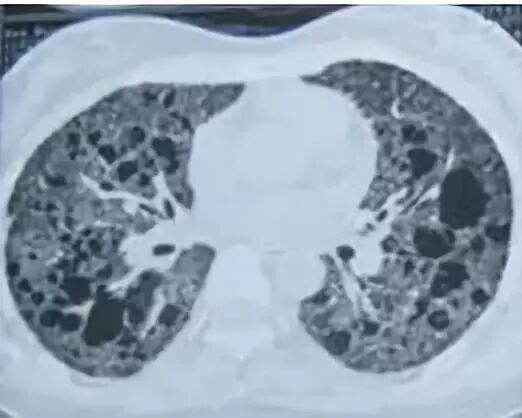

患者的肺像铺路石一样

这是肺内通气灌注不一致的表现,主要是小支气管炎症导致肺内局部积气,像马赛克拼图一样